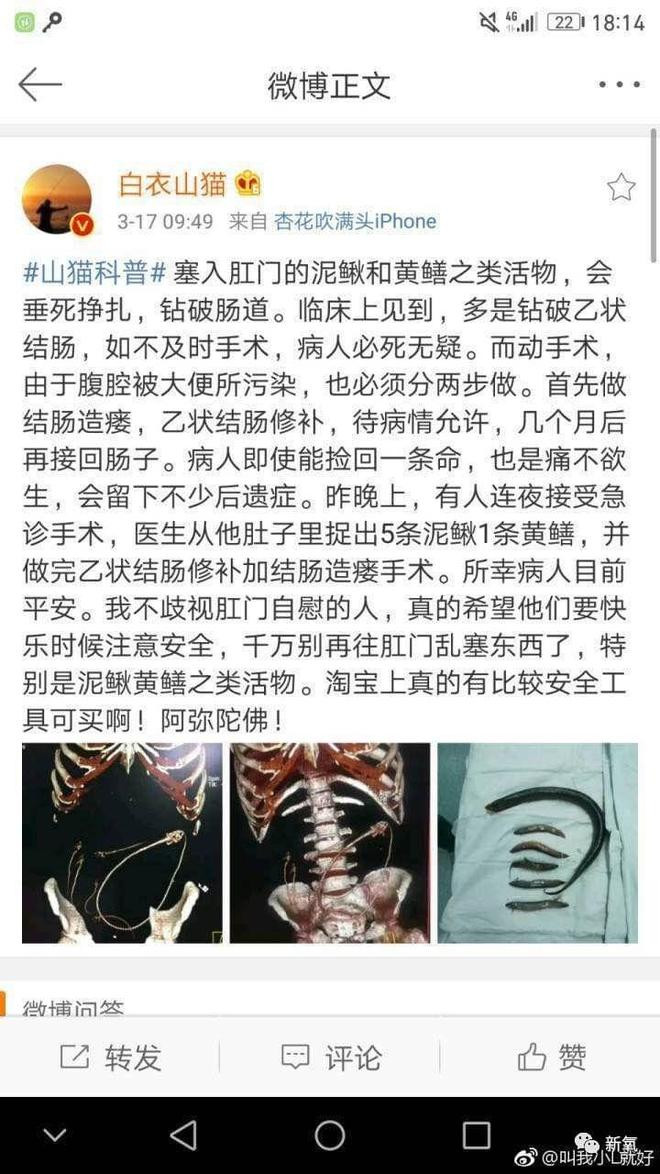

医生科普:塞入肛门的泥鳅和黄鳝之类活物,会垂死挣扎,钻破肠道。临床上见到,多是钻破乙状结肠,如不及时手术,病人必死无疑。而动手术,由于腹腔被大便所污染,也必须分两步做。首先做结肠造瘘,乙状结肠修补,待病情允许,几个月后再接回肠子。病人即使能捡回一条命,也是痛不欲生,会留下不少后遗症。

X光照片中黄鳝大逃亡,显然是在疯狂找出口。